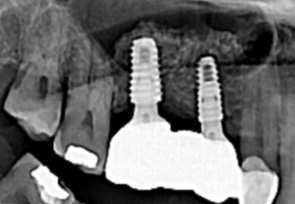

미국치과 임플란트 학회(AAID)의 인정의(AF. Associate.Fellow)인 일등플란트치과의 한순일 대표원장이 다 년간의 많은 임상경험 노하우를 바탕으로 구강 상태에 따른 적합한 뼈이식을 통해 임플란트에 적합한 뼈의 두께를 확보한 후 식립을 합니다.

잇몸뼈에 심은 임플란트가 잇몸뼈에서 단단히 고정되면 인공치아 보철물을 올려 치아부분을 완성합니다. 일등플란트 치과는 병원 내에 별도의 기공소가 있어 나의 자연 치아와 가까운 자연스러운 보철물을 빠르고 꼼꼼하게 제작합니다.